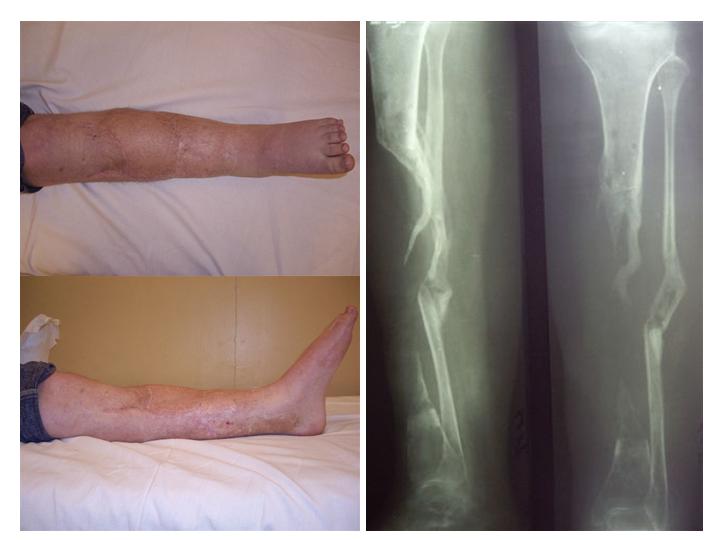

Пациентка с дефектом большеберцовой кости, возможно ли восстановление опороспособности нижней конечности?

ДТП 1.5 года назад: открытый оскольчатый перелом средней трети левой голени с дефектом мягких тканей.

4.Попытка устранения дефекта по методу Илизарова, нагноение, радикальная хирургическая обработка, увеличение дефекта.

6 месяцев без признаков гнойного воспаления. В настоящее время иммбилизация гипсовой лонгетой до коленного сустава, функция коленного сустава сохранена, голеностопного нет.